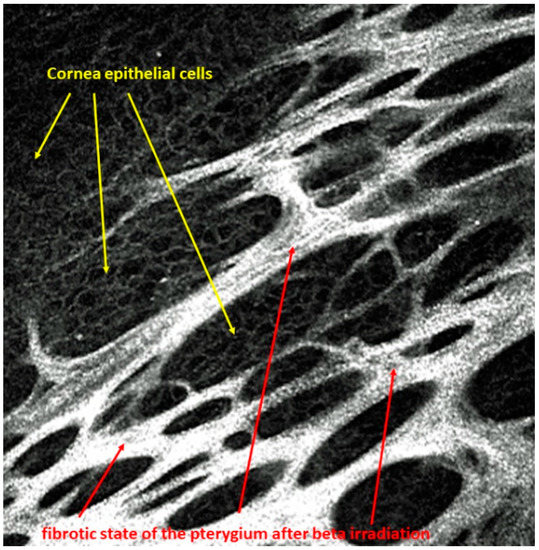

A pterygium grows proliferatively toward the center of the cornea with Bowman’s membrane as its guiding structure, which is destroyed [1,2]. A narrow zone at the head of the pterygium is vascular-free, while the base is vascular-rich. The base covers the peripheral cornea. However, the pterygium can be undermined. In particular, a confocal laser microscope can detect complete epithelial islands under the fibrous pterygium structures, as shown in Figure 1.

Figure 1.

Islets of corneal epithelial cells arranged within the fibrous structures of the pterygium after beta irradiation.

After beta irradiation, the pterygium appears as an avascular, fibrotic membrane, which is very sharply demarcated from the stromal structure of the cornea. The pterygium is fixed like a honeycomb to the pterygium head and to the stromal part in the area of the pterygium bed. Partially, the pterygium can be undermined and is lined with epithelial cells. By means of confocal microscopy, the layers of a pterygium can be visualized very well, from the superficial epithelial cells to the fibrotic structure of the pterygium with epithelial islands at a depth of 80 µm. At a depth of 100 µm, the underminable part is lined with epithelial cells reaching down to the sclera, which begins here at 120 µm (Figure 2). In a case series, it could be shown that on average, the pterygium thickness decreases by 40 μm after beta irradiation compared to the active, non-treated state. An average prominence of 120 μm remains after beta irradiation [3].